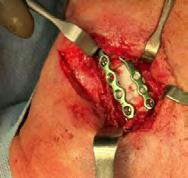

Se realiza una mandibulectomía parcial, con una incisión lineal donde se desperiostiza tratando de mantener nervio mentoniano íntegro, se procede a la extracción quirúrgica del cuerpo mandibular con osteonecrosis y osteomielitis, en el mismo acto

6a 6b 6c

quirúrgico se fija una prótesis hecha a medida de titanio con perforaciones para reconstrucción dental, se lava con una solución hiperóxidativa para microorganismos anaerobios, se coloca en Tissel para crear una barrera de fibrina, se colocó un drenaje tipo drenovac para evitar que haya edema, se sutura con vicryl 4-0.

A nivel oral se realiza sutura al nivel del reborde alveolar inferior izquierdo con vicryl 2-0 (Figura 4).

En los estudios imagenologicos se observó una adecuada consolidación de las placas con el hueso (Figura 6).